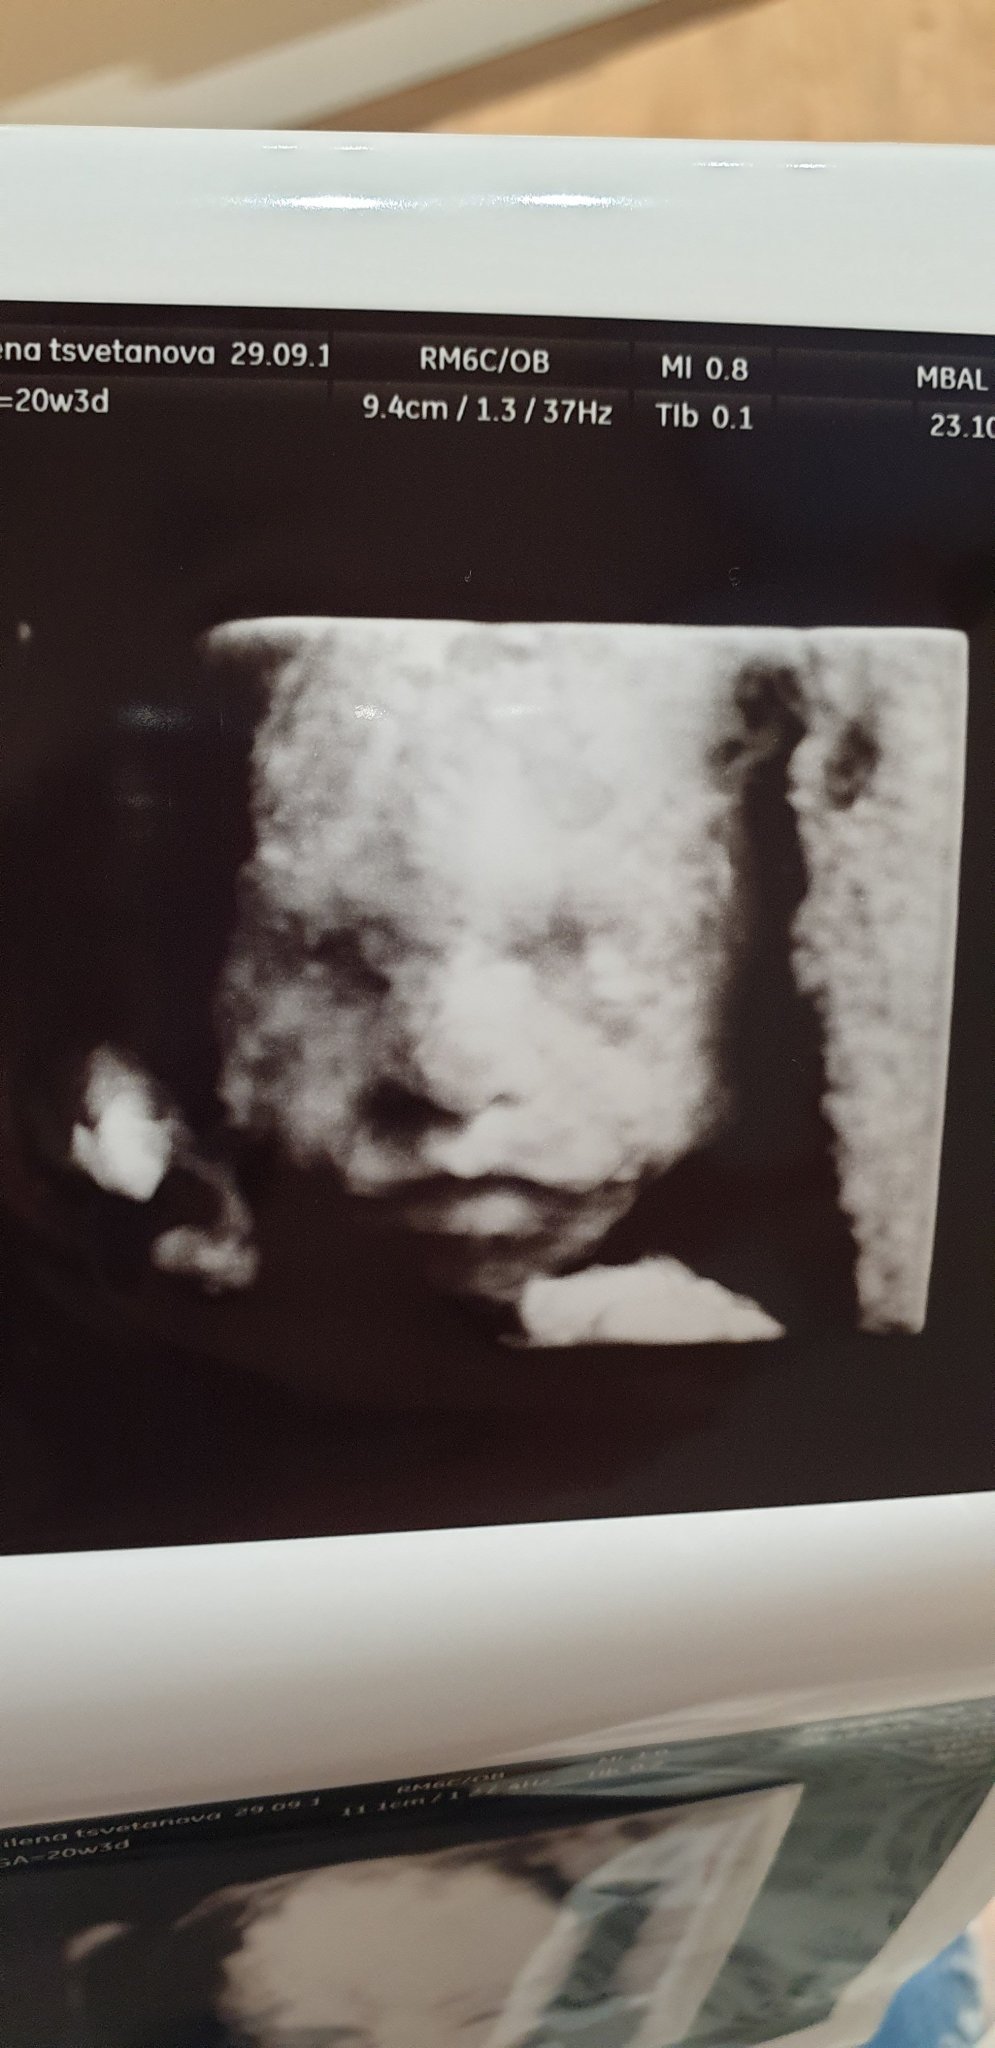

На апарата е цветно, ама ти ги печатат черно бяло, поне на мен. Аз мислих да не искам 3д снимка,  защото преди 25-6гс бебоците още нямат подкожни мазнини и някой снимки са плашещи Simple Smile Обаче моята изглеждаше приемливо Simple Smile Според таткото е зловеща тази снимка Simple Smile това е. Simple Smile . Зависи и как е застанал бебо, може да се крие с ръчички и да не се вижда личицето.